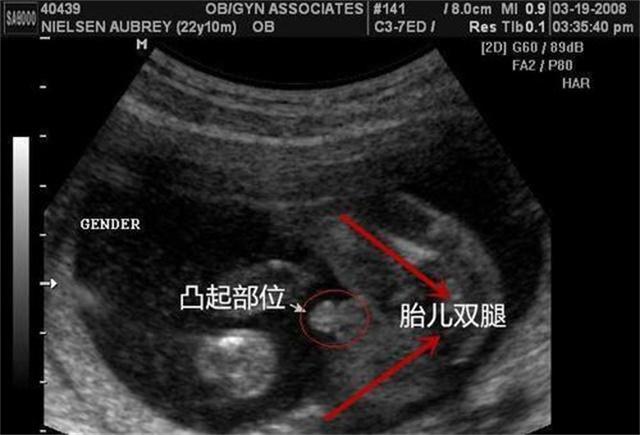

妊娠中の母親が、この議論に最もふさわしい立場にいることは間違いない。多くの妊婦は、脈拍妊娠検査を受けることは純粋に「心理テスト」であり、尿検査や超音波検査といった現代の医学的検査のほうが信頼できると言う。

"漢方脈で妊娠しているか診断してくれますか?"昨日、記者は広州の第二子出産QQグループで簡単な調査を行った。グループ内の計63人の母親が調査を受け入れたが、1人目も2人目も妊娠の漢方脈診を使ったことがある母親はいなかった。母親たちは、一般的に月経が来ていないことを発見し、最初の反応は、 "ヒット "かどうかを検出するために妊娠検査薬を使用することであると述べた。「妊娠検査薬は安くて精度が高く、何より便利で、薬局でも買える。妊娠検査薬は安くて精度が高く、便利で、薬局で買うことができる。越秀区に住む2児の母、黄毅さんは言う。

母親たちはまた、診断の確認のために漢方薬を使わなかった理由として、漢方薬は経験のみに基づくもので、正確率が高くないと感じたからだと述べている。西洋医学は技術的な手段で発見し、その結果はより正確である。さらに、超音波検査、血液検査などを通じて、"問題のある赤ちゃん "かどうかを検出することもでき、比較的、西洋医学の結果は直接的で、正確で、時間を節約することができます」。

脈拍は妊娠を診断することができるので、現在クリニックで適用されていますか?鄧聡の紹介によると、"健康な女性が妊娠しているだけで、診断が難しく、妊娠週数が増えるにつれて、脈拍はますます明らかになります。一般的に3ヶ月以上になると、脈が滑りやすくなります。"と紹介した。鄧聡は、現代医学の妊娠診断の使用は確かにはるかに安全であることを指摘し、純粋に脈拍は確かに少し一方的であり、その精度は統計されていない。

"脈を取ることが妊娠の診断に使われることは今ではほとんどなく、日常的な病気の診断と治療に使われるだけである。"妊娠可能な年齢の女性は、脈拍だけに頼って妊娠しているか否かを診断するのではなく、より確定的な診断を下すために、やはり生化学的検査(尿検査が便利)をもっと頻繁に参照すべきであると提言している。「結局のところ、脈を通じて死産か生きた胎児かを感じ取ることができるだけであり、先天性の心臓や遺伝病、奇形などがあるかどうかは、現代医学を通じてのみ診断できるのである。

鄧博はまた、中国の病院であろうと西洋の病院であろうと、臨床基準における妊娠の診断において、「脈拍妊娠検査の診断」がないことは確かであり、妊娠診断のゴールドスタンダードは尿検査、血液検査、超音波検査の3つであると述べた。